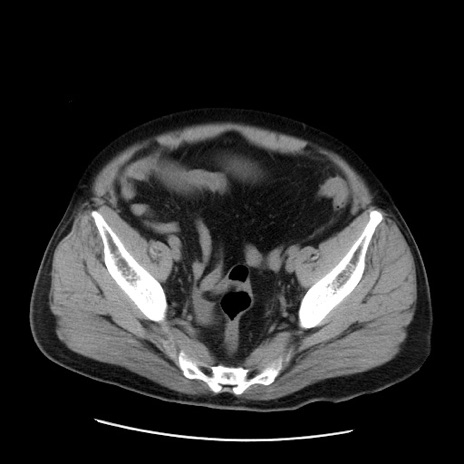

症例20(横断像)

【症例】 60歳代男性

【主訴】 腹部膨満、嘔吐

【現病歴】5日前頃より倦怠感を認め食事量減少し4日前の朝嘔吐、食事摂取困難となった。 3日前近医受診し点滴施行され整腸剤などを処方された。 当日他院を受診し、腹部膨満著明、炎症反応の上昇(CRP10.8、WBC11200)あり、紹介受診となる。

【身体所見】 意識JCS1 受け答えがはっきりしないBP 111/57mHg、 P 67bpm、、BT35.2°C、SpO2 97%(RA)、 腹部:膨隆、打診で鼓音あり、全体的に圧痛有り、腸蠕動音(-)、反跳痛ははっきりせず。

【データ】WBC 11400、CRP 14.20